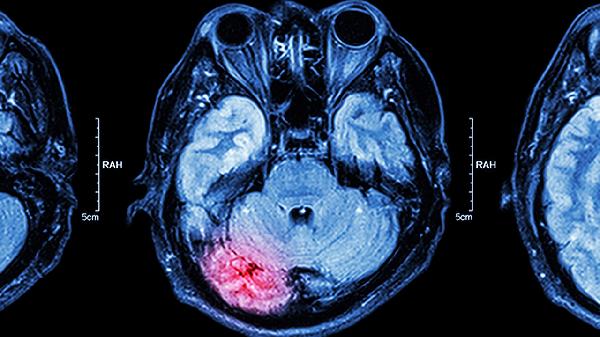

腦供血不足可能與枕頭高低有關(guān),但通常不是主要原因。腦供血不足多由動脈硬化、頸椎病、高血壓等因素引起,枕頭高度不當可能加重頸椎問題,間接影響腦部供血。

枕頭過高或過低可能改變頸椎生理曲度,壓迫椎動脈或頸交感神經(jīng),導致椎基底動脈供血不足。長期使用過高枕頭可能使頸部前屈,椎動脈受壓,減少腦部血流;過低枕頭則可能使頸部過度后仰,影響靜脈回流,增加顱內(nèi)壓。這類情況多見于已有頸椎病或血管狹窄的人群,表現(xiàn)為頭暈、視物模糊等癥狀,調(diào)整枕頭高度后可能緩解。

少數(shù)情況下,枕頭高度可能成為腦供血不足的誘因。例如睡眠時頸部長時間扭曲,導致椎動脈機械性壓迫,引發(fā)短暫性腦缺血發(fā)作。這類情況通常伴隨體位性頭暈,改變睡姿后癥狀迅速消失。但需注意,單純枕頭問題極少直接導致慢性腦供血不足,更多是與其他血管風險因素共同作用。